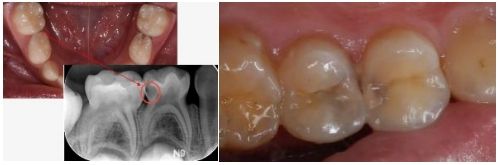

2.位置的欺骗性:

很多龋病发生在牙齿的邻面(牙缝之间)或者后牙的窝沟深处,这些地方肉眼很难直接看到。只有当洞扩大到一定程度,您用舌头才能舔到,或者食物开始塞牙时,您才会“突然”发现它。